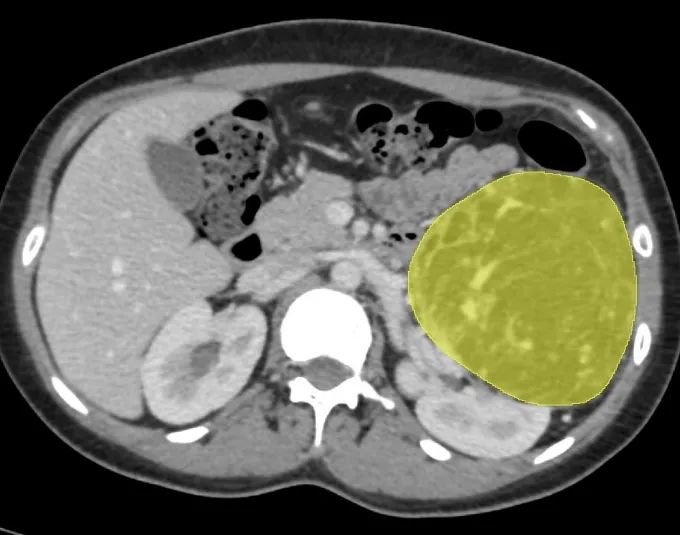

传统二维影像难以全面展示肾动脉分支、静脉变异及集合系统分布等空间关系,而这对肾肿瘤手术规划至关重要。

相较于传统的二维图像,三维可视化模型具备更直观、更精确的特点。模型可以实现全方位旋转、任意缩放和组合显示,能够清晰展示肿瘤的大小、形态,血管的走向和形态,更深入地揭示肿瘤与周围器官及血管的解剖关系和侵犯情况,减少了医生在解读原始CT图像时可能出现的主观失误,使术前评估更加真实可靠。

三维重建可辅助手术规划设计,通过三维重建,可以提供更多关于肿瘤的信息,包括肿瘤边界整体形态、血液供应情况以及与肾血管的关系。

三维重建技术可以精确观察肾血管的起始位置及走形、数量和间距,从而选择合适的阻断血管及阻断位置,减少因阻断不全而引起的出血。

三维重建技术展现出其独特的优势,能够更为直观、准确地展示肿瘤位置以及与周围血管之间的关系,为手术决策提供有力的支持。